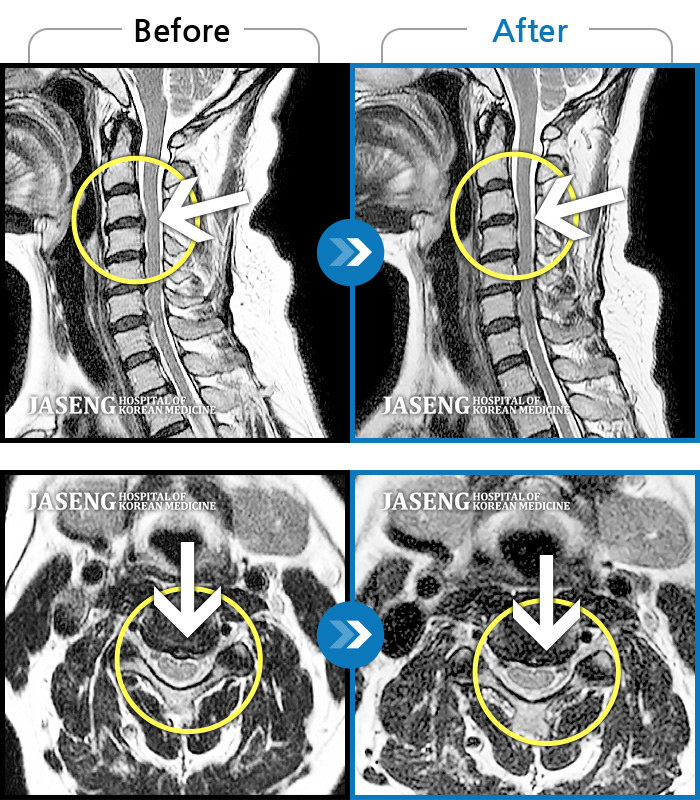

목디스크

강남 · 강만호 원장

양측 승모근 통증과 목 통증, 견갑골 통증으로 고개를 돌릴때 통증을 호소하는 환자였습니다.

촬영시기

2019.11.18 ~ 2024.07.30

2024.08.09

조회수 478